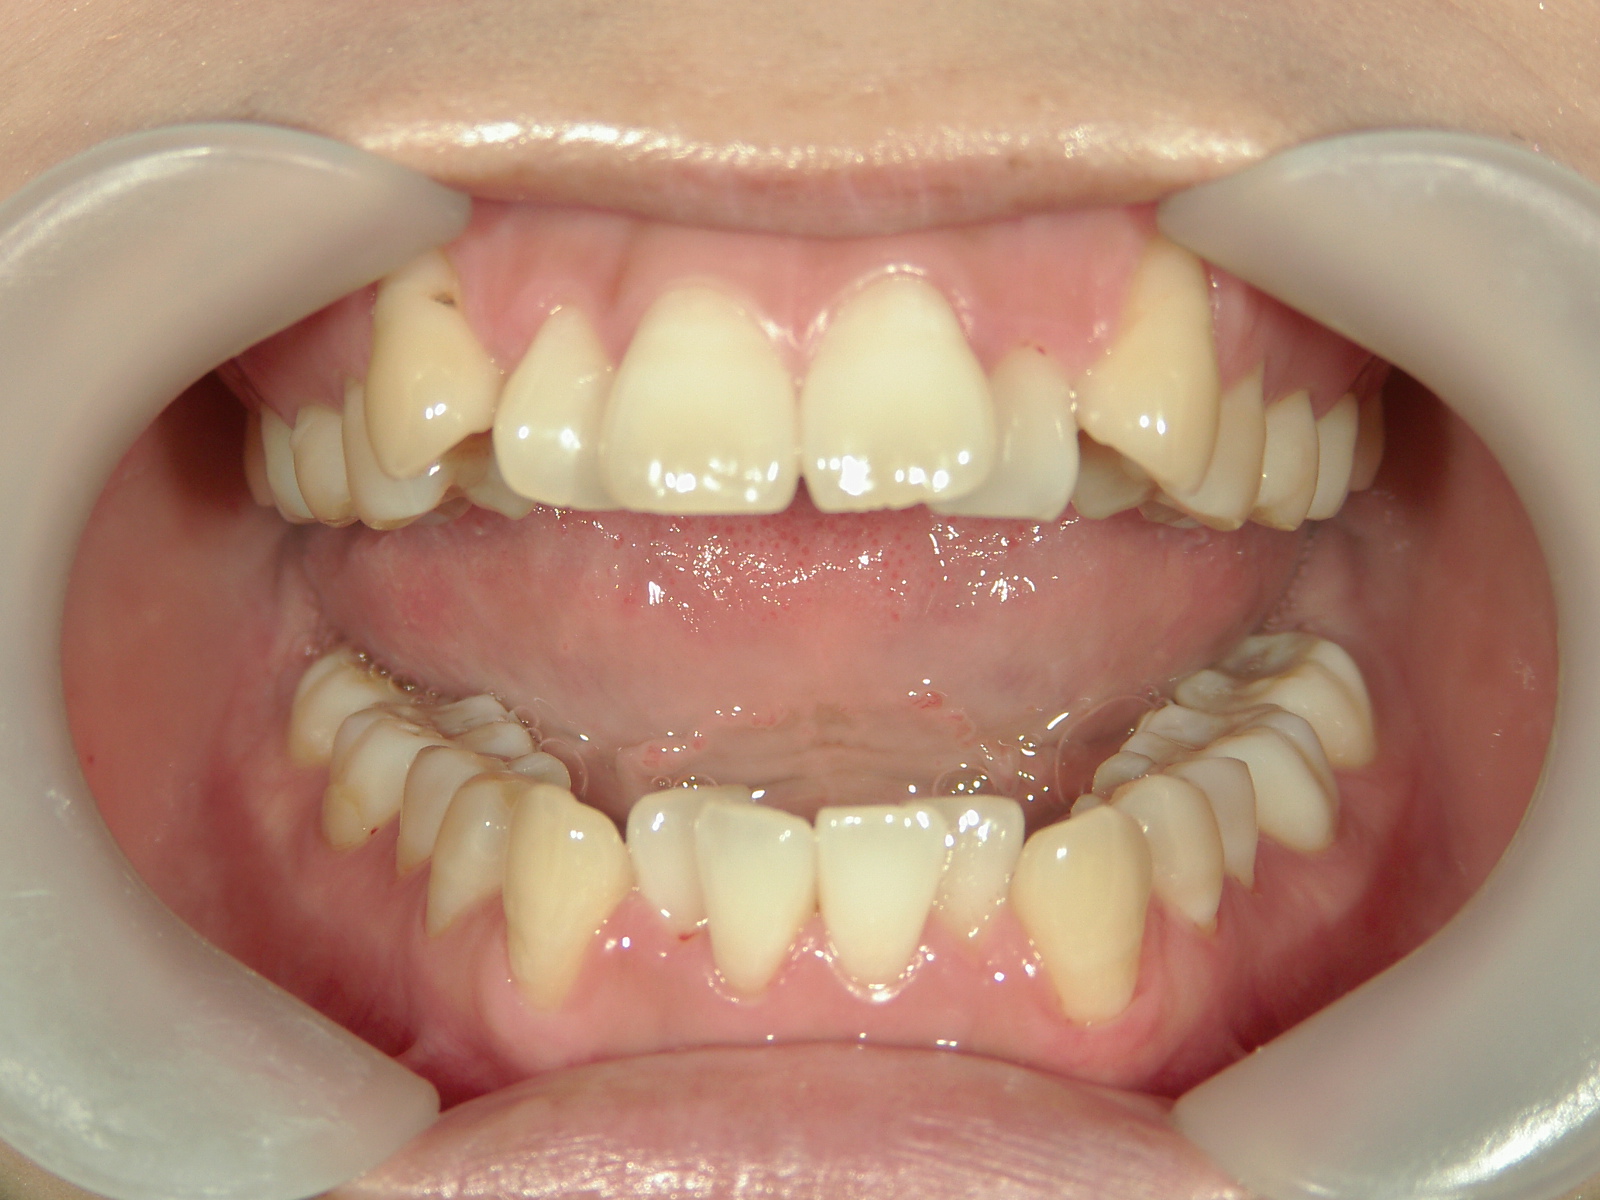

プチワイヤー矯正 症例(53)

| 治療期間 | 9ヶ月 |

カテゴリー : ガタガタ(叢生)